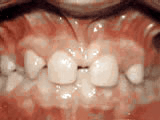

Phase One

Patient's parents were concerned about both aesthetics and the health of the erupting permanent teeth when they brought him to the orthodontist at age eight. The lower front teeth were crowded and touching the palate, and the upper front teeth were extremely displaced from their normal positions. After 12 months of Phase One treatment with an expander and partial braces, patient's appearance and dental function were vastly improved.